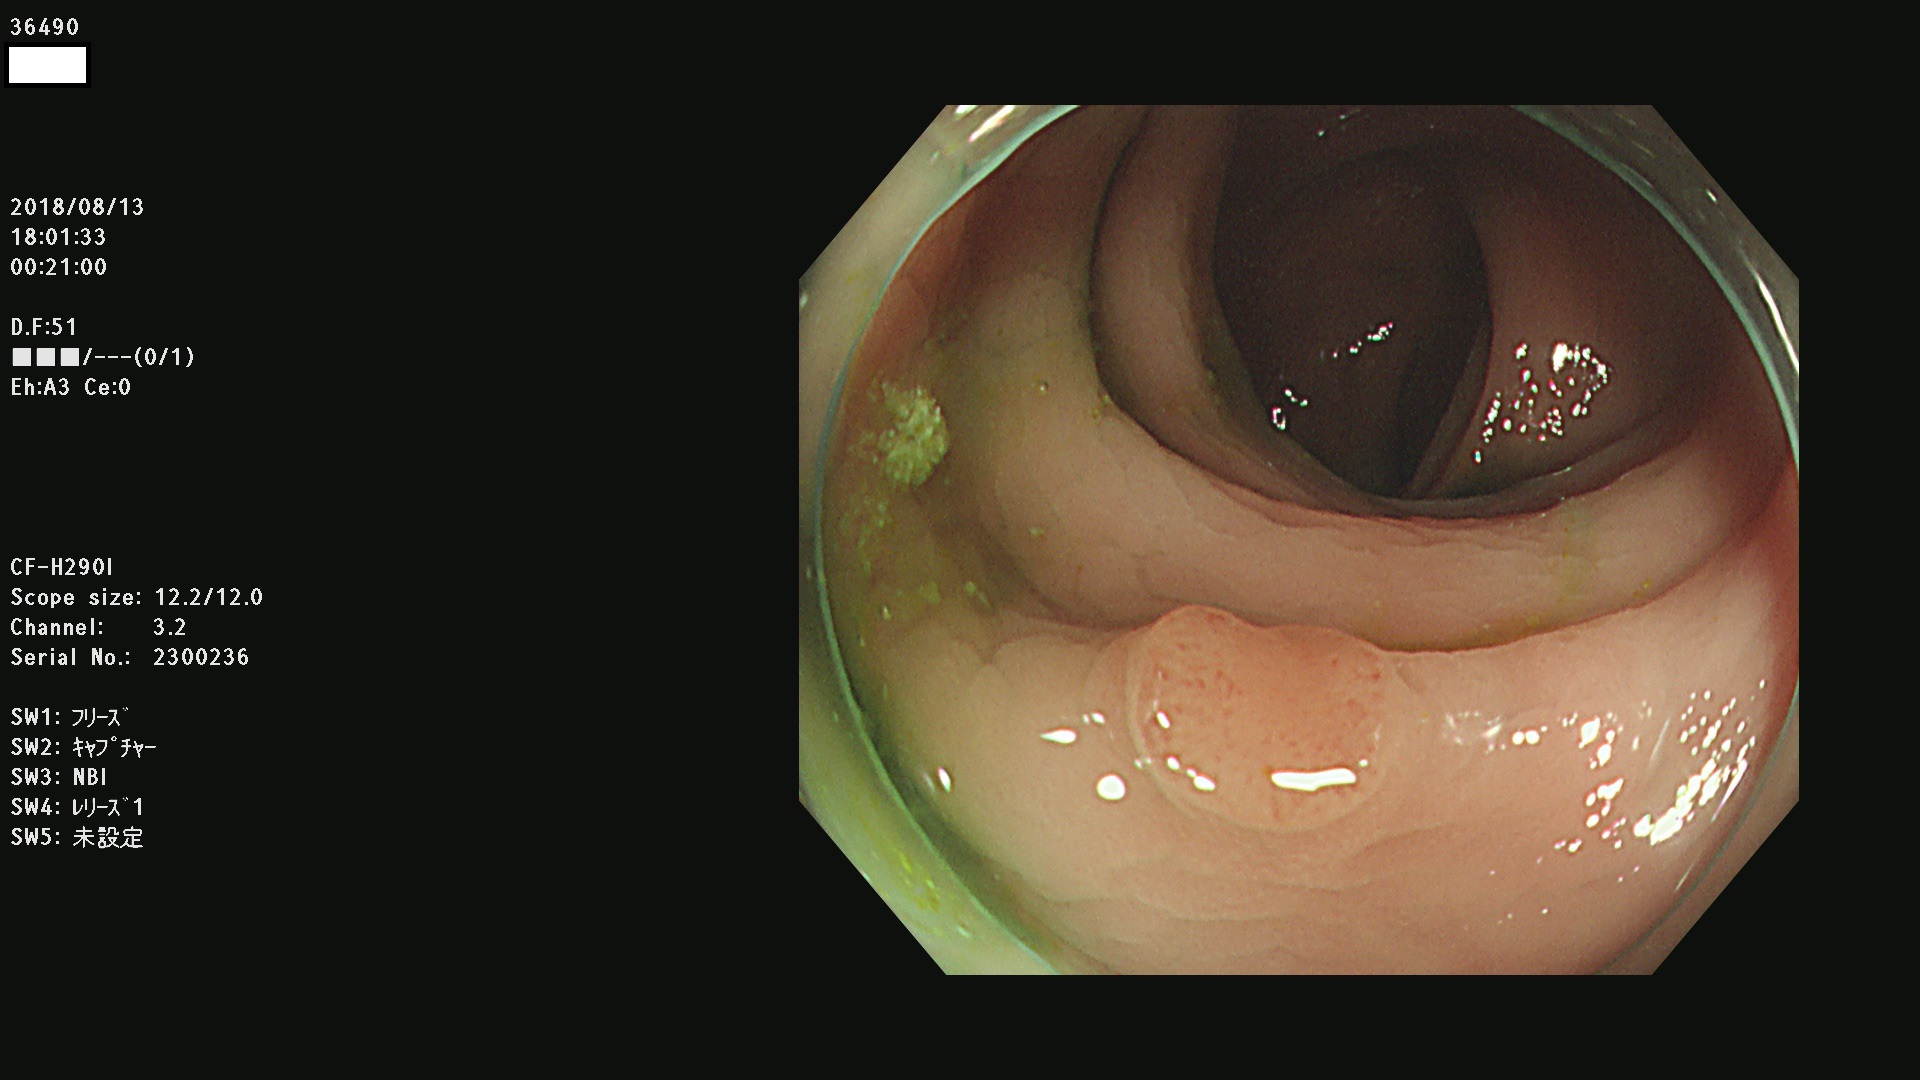

36400(SSAPのみ) 36402 36403 36404 36405 36406 36407 36408(SSAPのみ) 36412 36413 36414 36415 36416 36417 36418 36420 36422 36423 36424 36425 36426 36428 36429 36430 36431 36434 36435 36436 36437 36438 36440 36443 36447 36448 36449 36450 36452 36454 36458 36459 36460 36462(SSAPのみ) 36463 36464 36465 36466 36470 36471 36472 36473 36474 36475 36476 36478 36480 36481 36482 36484 36487 36488 36489 36490 36492 36494 36495 36496 36497 36498

発見困難で危険性の高い平坦型病変(上記100名より抽出)